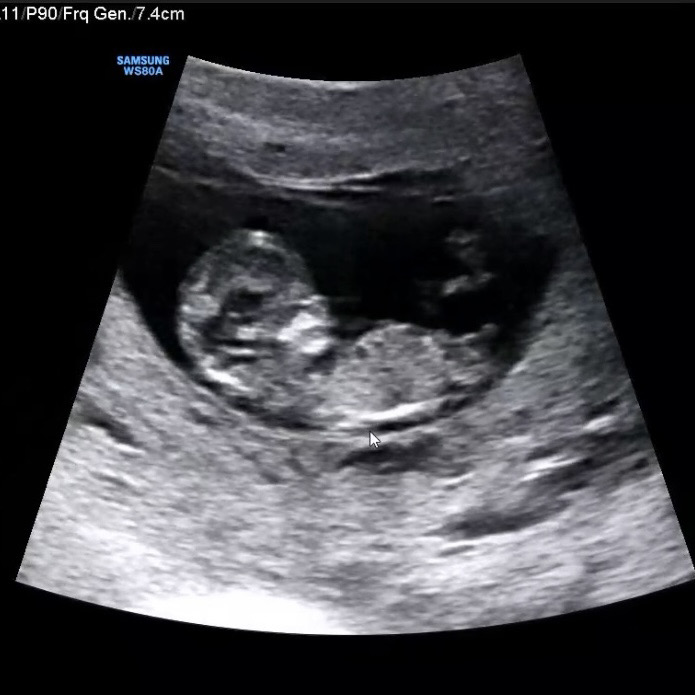

11주 초음파 성별 예측 궁금해요! 딸vs아들

주변에서 딸이다! 아들이다! 의견이 나오고 있어요! 각자 의견 하나씩 남겨주시면 감사하겠습니다! 💛

아들같아요